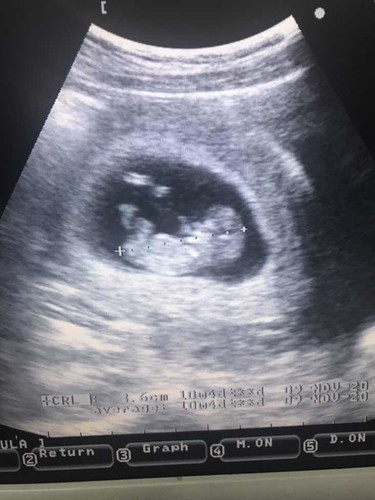

น้องดิ้นตอน 10wk ++ เร็วไปไหมค่ะ ??

ขอบคุณทุกคนที่ให้คำแนะนำนะคะ หลังจากมีตกขาวสีน้ำตาล ก็รีบไปหาคุณหมอ เป็นภาวะแท้งคุกคามจริงๆ ด้วยค่ะ คุณหมอฉีดฮอลโมนกันแท้งให้ และให้วิตามินมาบำรุง อุลตร้าซาวแล้วน้องแข็งแรงดี คุณหมอบอกดิ้นเก่งด้วยค่ะ ดีใจที่ไม่เป็นอะไร

ปรกติค่ะ เราซาวตอน 12 วีค หมอบอกน้องกำลังดิ้น ขยับแขนขยับขาค่ะ

ปกติค่ะ เพียงแต่แม่จะยังไม่รู้สึก เพราะน้องยังเล็กมากๆๆค่ะ

ปกติค่ะ เราไปซาวด์ตอน9w3d ก้เห็นน้องขยับดุ๊กดิ๊กแล้วค่ะ

ดิ้นตอน 10 w เหมือนกันคะ หลบไม่ให้หมอซาวด้วย😁